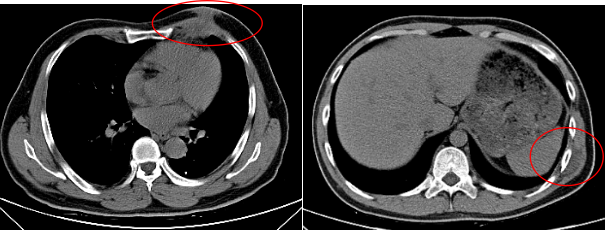

低热乏力胸痛你以为是结核其实是肿瘤惹的祸

图片尺寸611x615